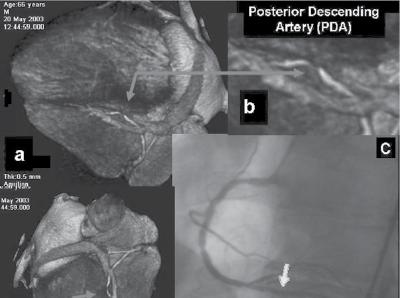

Figure 1.1 (A) Normal case: coronary angiography (left) and three‐dimensional CTA (right) showing normal left anterior descending (LAD, arrow) and left circumflex (LCX) coronary arteries. The latter is partially covered by the left appendix in CTA. (B) Normal case: coronary angiography (left) and CTA (right) showing a normal dominant right coronary artery (RCA). (C) An 85‐year‐old man with atypical chest pain: (a) Maximal intensity projection (MIP) of CTA with tight mid‐LAD stenosis that correlates perfectly with coronary angiography (b). (D) Similar case as (C) but with the stenosis in the proximal RCA. (a–d) CTA and (e) coronary angiography. (E) A patient with tight stenosis in the LCX before a bifurcation. (a) and (b) CTA and (c) coronary angiography. (F) These images show that CTA may also demonstrate the presence of stenosis in distal vessel branches, in this case in the posterior descending branch of the RCA. (a–b) CTA and (c) coronary angiography. (G) These images show that CTA (a, b) may delineate the length of a total occlusion and visualize the distal branches (see arrows in (b)). Collateral flow from the LAD to the RCA may be better visualized with CTA than with conventional coronary angiography (c: here only the RCA is shown). (H) A 42‐year‐old patient with a stent implanted in the LAD six months before. The patient complained of atypical chest pain and underwent CTA. The MIP images of CTA (a–c) show no significant restenosis, but some plaque formation in the left main trunk (d, circle) that was not well seen in coronary angiography (e). The degree of luminal obstruction by the plaque can be exactly measured by intravascular ultrasound (IVUS) (f). The ECG showed mildly inverted T waves in V1–V3 during follow‐up (see Plate 1 in color plates).